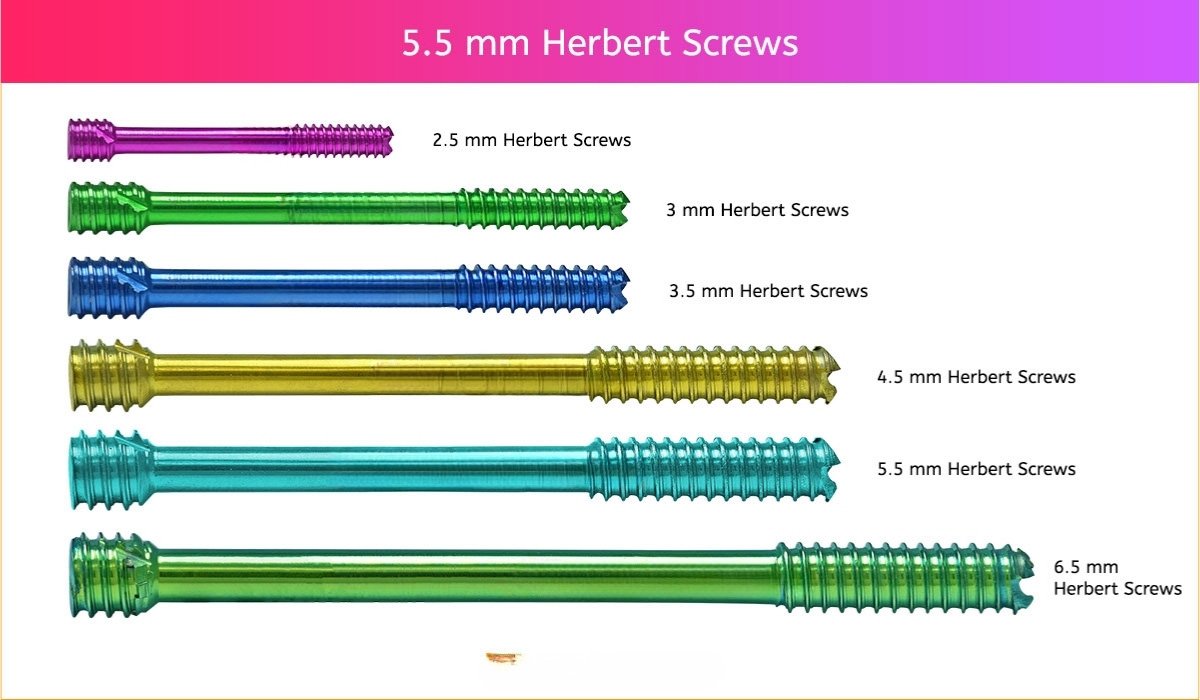

5.5 mm Herbert Screw

5.5 mm Screws Length

12mm, 14mm, 16mm, 18mm, 20mm, 22mm, 24mm, 26mm, 28mm, 30mm, 32mm, 34mm, 36mm, 38mm, 40mm, 42mm, 44mm, 46mm, 48mm, 50mm, 55mm, 60mm, 65mm, 70mm, 75mm, 80mm, 85mm, 90mm, 95mm, 100mm, 105mm, 110mm, 115mm and 120mm.

- 5.5 mm and 6.5 Herbert Screws are indicated for fracture fixation, reconstruction, osteotomy, and arthrodesis of various bones and bone fragments including joint fusions (arthrodeses) in the foot and fixation of intra-articular fractures of the humerus, femur and tibia.